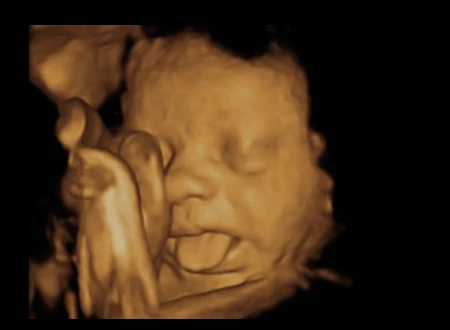

Trong bức ảnh thú vị này, ta có thể nhìn thấy em bé này đang lè lưỡi trêu đùa.